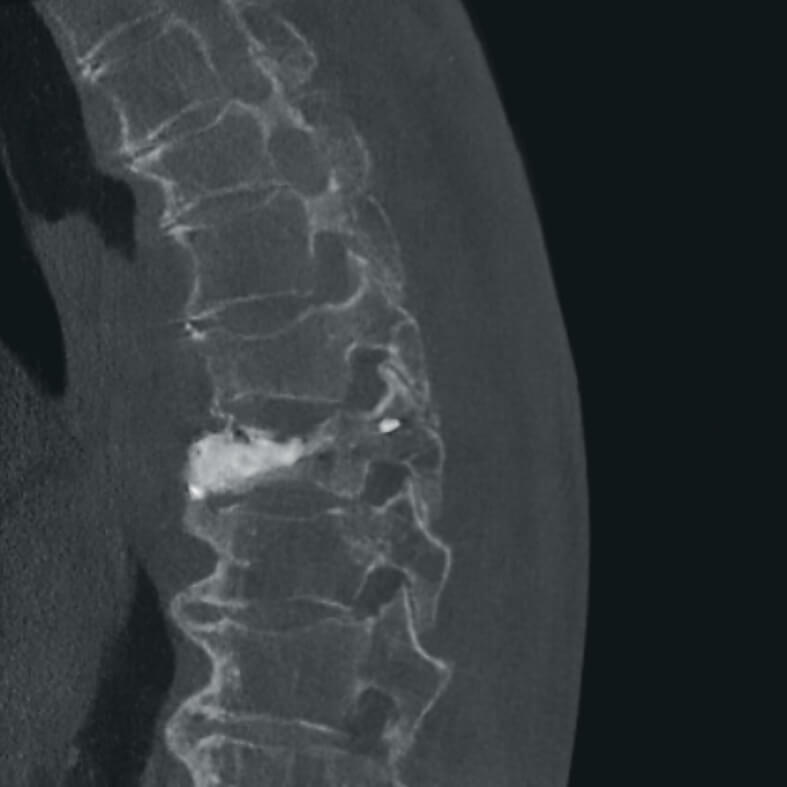

Полное отсутствие искажений снимков в сочетании с высоким динамическим диапазоном широко востребованы как при сложных операциях в нейрохирургии, сосудистой хирургии, инвазивной радиологии, так и в гибридных областях применения, а также в ортопедии, травматологии. В сосудистой хирургии особенно важны высокий динамический диапазон и пространственное разрешение, обеспечивающие детальную визуализацию даже мельчайших сосудов. Специализированное программное обеспечение SmartVascular позволяет проводить настройку системы для васкулярных операций и сосудистой хирургии.

Точная визуализация анатомических деталей, мягких тканей и костных структур обеспечивается за счет светочувствительной матрицы 3kх3k пикселей с высоким динамическим диапазоном.

- вертебрология,